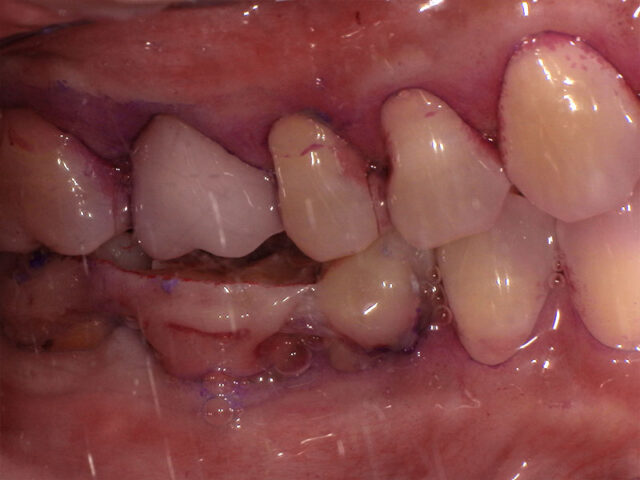

口腔内写真(術前・移植前)